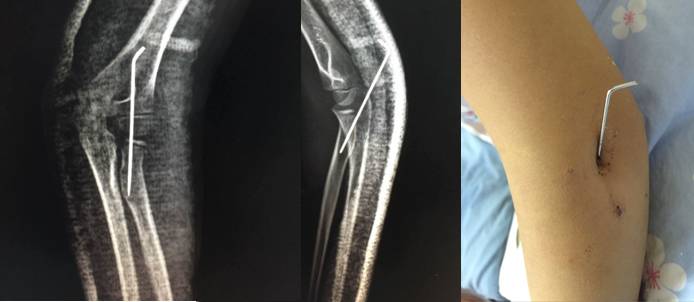

8 岁女孩桡骨颈骨折。

接近 90 度(>30度)成角的桡骨颈骨折,仍首先尝试 Patterson 与以色列法等闭合复位方法.

难推动倒斜下的桡骨颈,闭合复位失败,2.0 克氏针扁头经皮撬拨骨折断端,克氏针钝头复位骨折。

取出复克氏针,已经比较稳定,但侧片看见桡骨近端仍有轻微向后、外移位趋势,存在潜在不稳定。

1.5 克氏针固定,避免向后外移位趋势(术后正、侧位X线片及置针的肘部外观)

很显然我们按红箭头走了 Timothy 的路线图。